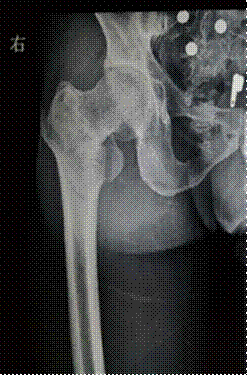

典型病例:1.患者,女,62岁,入院诊断“右股骨中下段粉碎骨折”。

图1:术前X线片 图2:术后侧位片 图3:术后正位片

2.患者,男,35岁,入院诊断“右股骨粗隆间粉碎骨折”。

图5:术前X线片 图6:术后X线片